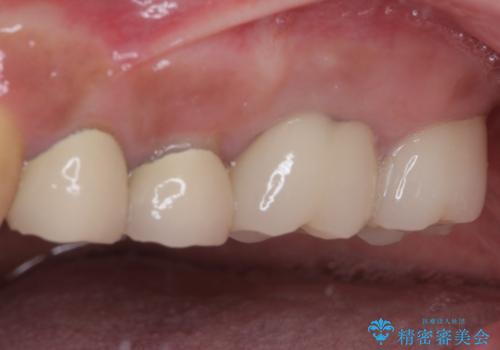

インプラントや歯周外科処置を用いた奥歯の補綴治療

治療後は痛みなどなく、快適に噛めるようになりました。

左右ともに歯根が破折しており、抜歯が必要であったため、抜歯後にインプラント補綴治療を行うこととしました。

左上は当初治療予定ではありませんでしたが、クラウンの周りに汚れがたまっていることが気になってきたため、追加して治療を行うこととしました。